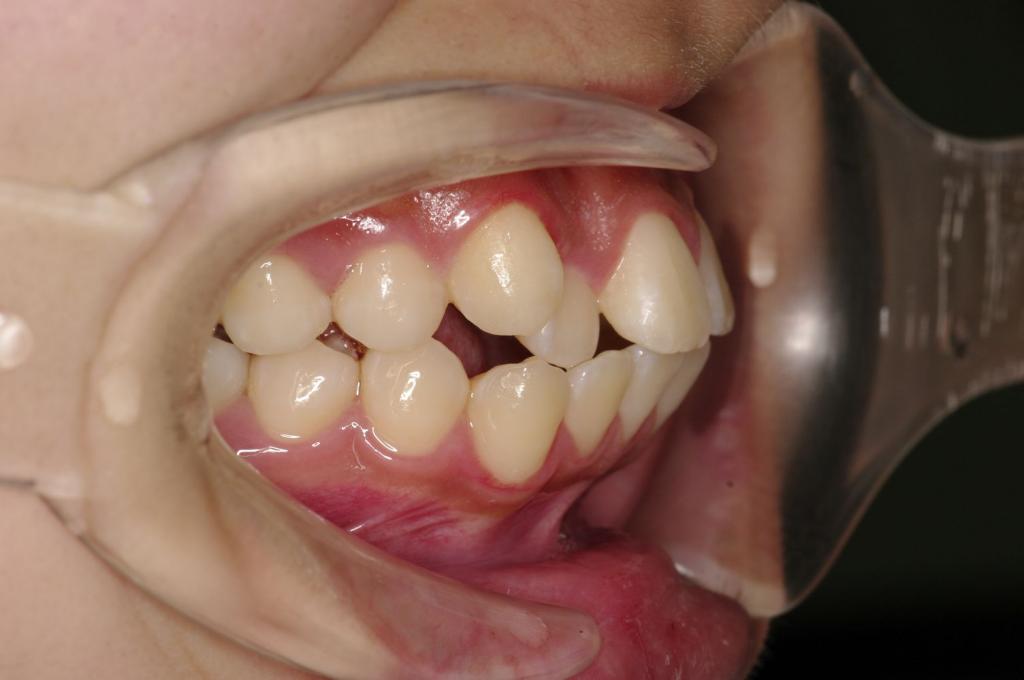

前歯、出っ歯・開咬の矯正治療

(治療期間、治療前後写真、治療方法、費用)WORKS